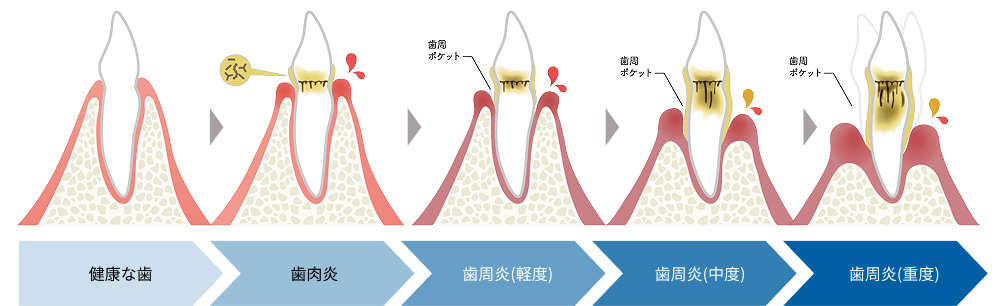

気づかぬうちに進行する歯周病

歯周病は、歯を支える歯ぐきや骨に炎症が起き、やがて支えを失って歯が抜け落ちる病気です。

初期段階では「歯ぐきの腫れ」や「出血」といった軽い症状が現れますが、

進行すると以下のような状態になります。

たかた歯科医院では、歯周ポケット検査やレントゲンを用いて、

見た目ではわからない歯周病の進行度を丁寧に診断し、状態に応じた治療を行います。